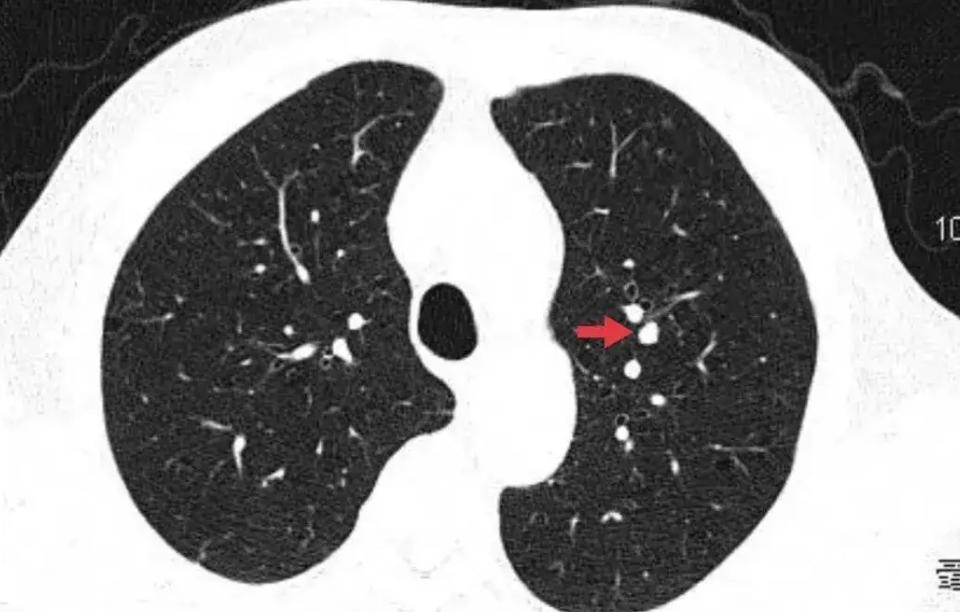

From www.researchgate.net

Peripheral lung nodules in the right upper lobe of a patient (arrow What Is Lung Nodular Density  It measures up to 3 centimeters in diameter, and if larger, is. A lung nodule is a small growth in the lung that can show up on a ct scan. A lung nodule is a small mass of dense tissue on the lung. Commonly called a “spot on the lung” or a “shadow,” a nodule is a round area that. What Is Lung Nodular Density.